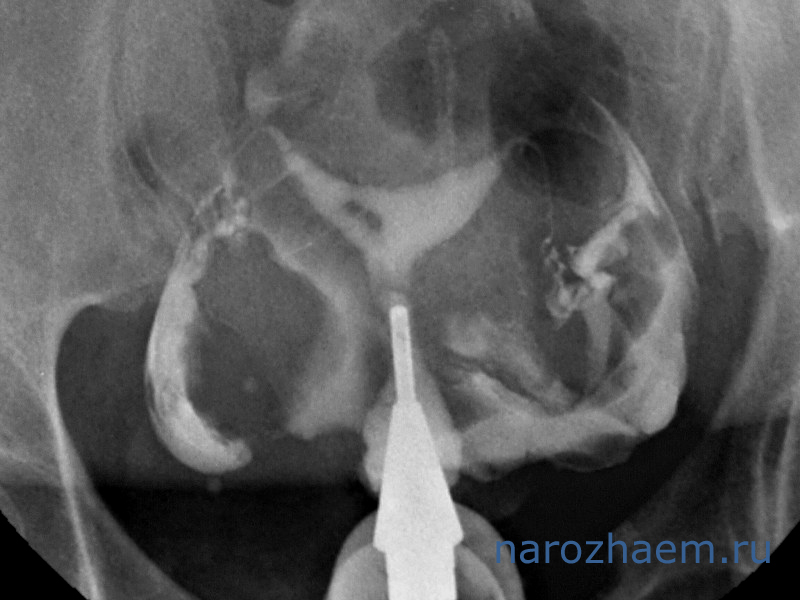

- рентгенологический – метросальпингография;

Рассмотрим каждый из этих методов более подробно. Одним из самых первых, которые использовались с этой целью, являлся рентгенологический. Его суть заключалась в том, что в полость матки вводилось рентгенконтрастное вещество, а затем оценивалось его поступление в брюшную полость. Основными недостатками этого метода являлись:

- получение ложно положительных результатов в 20% случаев, которые были обусловлены рефлекторным спазмом маточных труб, а не их истинной непроходимостью;

- возможное развитие аллергических реакций на йод, который входит в состав рентгенконтрастного вещества;

- в некоторых случаях развивался спаечный процесс в просвете маточной трубы на используемый контраст, что в итоге приводило к трубному бесплодию.